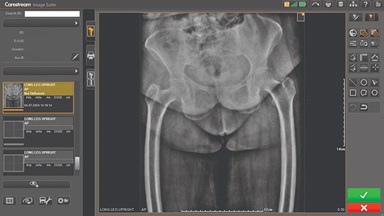

We’re thrilled to announce the launch of our newest campaign, spotlighting Carestream’s Focus Detector Retrofits with Image Suite Software, which is purpose-built for veterinary applications. This initiative celebrates not only our cutting-edge imaging technology—but also the deep, healing bond between humans and their pets.

At Carestream, we recognize that pets are family, and their health deserves the same level of care and innovation as any human patient.

Upgrading your imaging system to a solution designed for outstanding image quality is no longer out of reach — it's now easier, more affordable, and more effective than ever before.

Our Carestream Focus HD 35/43 Retrofit Detectors, powered by Image Suite Software, are an ideal solution to step up to full digital X-ray for customers who simply cannot compromise on image quality. It seamlessly integrates into existing setups, bringing the power of full digital X-ray with minimal disruption and maximum clarity, along with the following benefits: